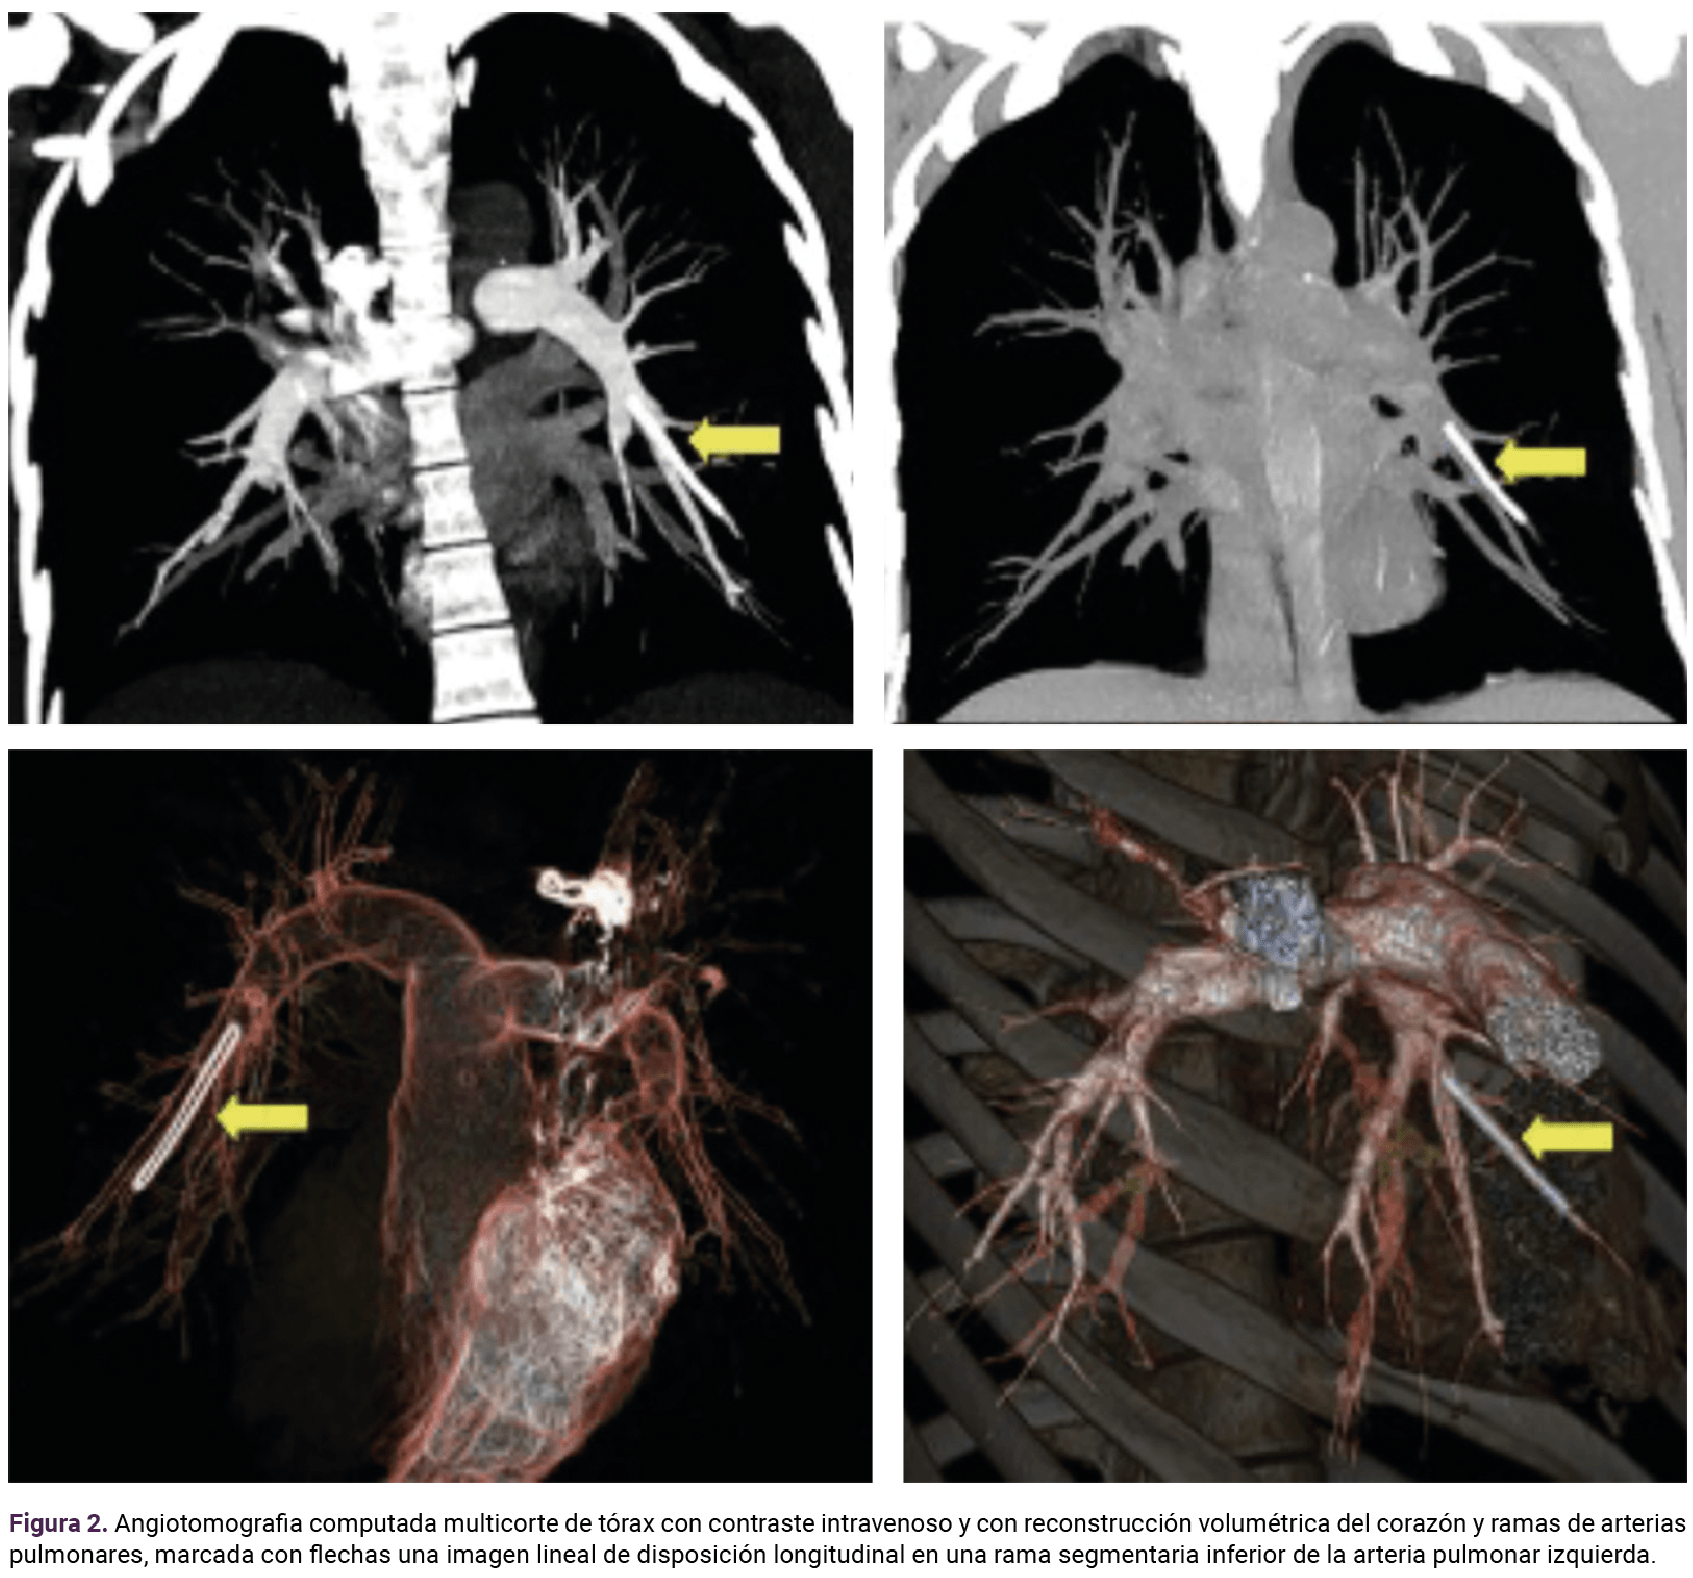

En la valoración integral de la paciente se advirtieron indicios de dificultad respiratoria, con polipnea al momento de esfuerzos físicos de pequeña intensidad. La angiotomografia computada de las arterias pulmonares, indicada por la imagen sugerente de implante subdérmico en torno del parénquima pulmonar y que se corroboró en la rama de la arteria pulmonar izquierda. Figura 2

<strong>Figura 2</strong>

Figura 2